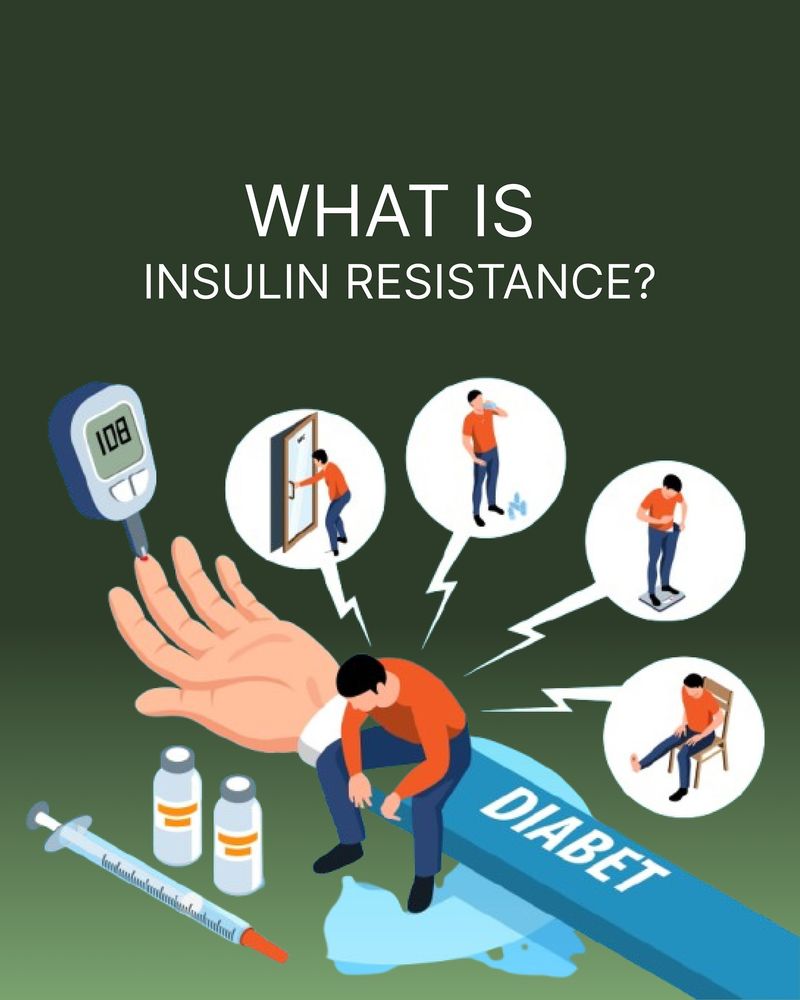

16. Insulin Resistance

Insulin resistance can sneak up on you, often tied to a diet too rich in carbs. High-carb meals can cause insulin levels to rise, gradually diminishing your body’s sensitivity. To improve your insulin response, cut back on refined carbs and opt for fiber-packed foods.

This approach can boost metabolic health and lower the risk of type 2 diabetes, creating a foundation for better insulin sensitivity and overall well-being.